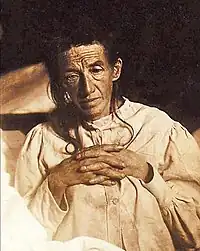

History

The ancient Greek and Roman philosophers and physicians associated old age with increasing dementia.[26] It was not until 1901 that German psychiatrist Alois Alzheimer identified the first case of what became known as Alzheimer's disease, named after him, in a fifty-year-old woman he called Auguste D. He followed her case until she died in 1906 when he first reported publicly on it.[230] During the next five years, eleven similar cases were reported in the medical literature, some of them already using the term Alzheimer's disease.[26] The disease was first described as a distinctive disease by Emil Kraepelin after suppressing some of the clinical (delusions and hallucinations) and pathological features (arteriosclerotic changes) contained in the original report of Auguste D.[231] He included Alzheimer's disease, also named presenile dementia by Kraepelin, as a subtype of senile dementia in the eighth edition of his Textbook of Psychiatry, published on 15 July, 1910.[232]